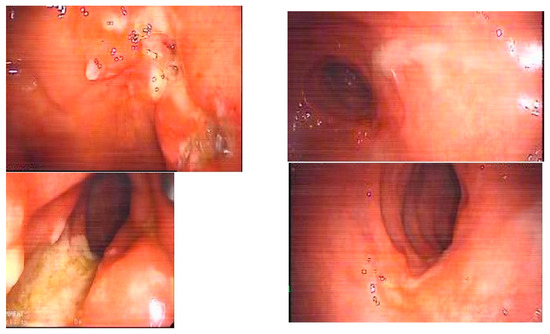

- Hüseyin, S.B. Intracolonic Bifidobacterium application can provide mucosal healing in inflammatory bowel disease. Gastroenterology 2019, 156, 30. [Google Scholar]